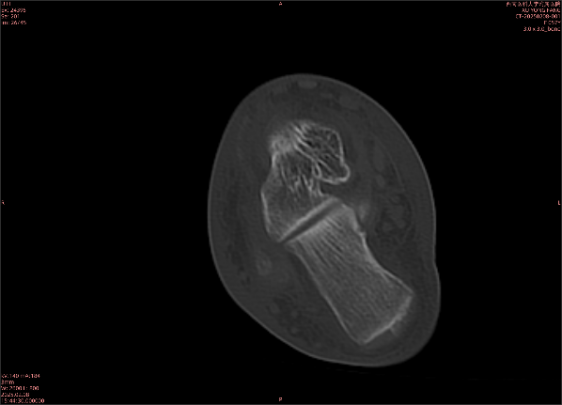

為什么DR和CT基本無法診斷?(專業(yè)科普)

由于無骨皮質(zhì)中斷,尚不足以引起X線衰減系數(shù)的明顯改變,X線平片無異常征象;CT在顯示骨皮質(zhì)及軟組織異常方面明顯優(yōu)于傳統(tǒng)X線,特別是三維重建能夠有效的評價(jià)復(fù)雜骨折,骨外傷CT檢查應(yīng)用廣泛,但CT對隱性骨折的顯示亦極為有限。

舉例圖像

圖2

專業(yè)解釋看不懂沒關(guān)系,大家看圖1和圖2就可以了,這是同一個(gè)患者跟骨的磁共振和CT圖像,圖1的紅色箭頭指示的黑線就是磁共振圖像顯示的骨折線,一目了然。而對比圖2的CT圖像上并未顯示異常。

這下大家明白了吧,如果懷疑隱匿性骨折優(yōu)先選擇磁共振檢查